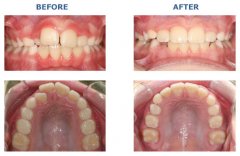

牙齿不齐原因多,矫正治疗需及时

在当今世界,一副整齐的牙齿,漂亮的面型不仅有利于牙周健康的维护,而且是...【详细】